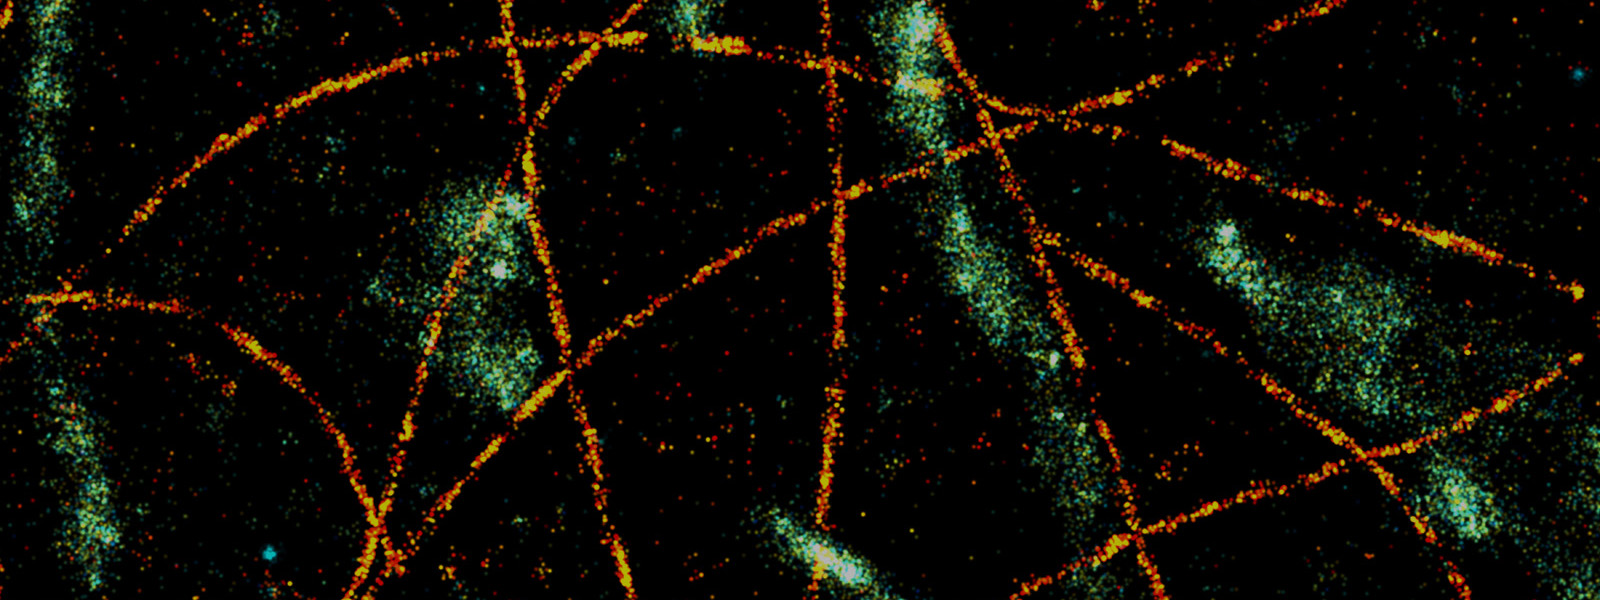

Intelligent Biomedical Optical Imaging and Diagnostics

光子学和光学成像的迅速发展为生物医学研究和临床诊断提供了前所未有的清晰度和调查能力。我们的研究兴趣在于开发新型光子器件和功能性光学成像平台,结合人工智能方法,旨在突破当前生物医学光学成像的限制,以提供从分子到细胞、组织、器官以及器官系统等不同尺度上日益增加的分辨率、灵敏度和特异性需求。我们期望这些新能力能够帮助我们建立起对生物系统的基础理解,进而应用于医学诊断。